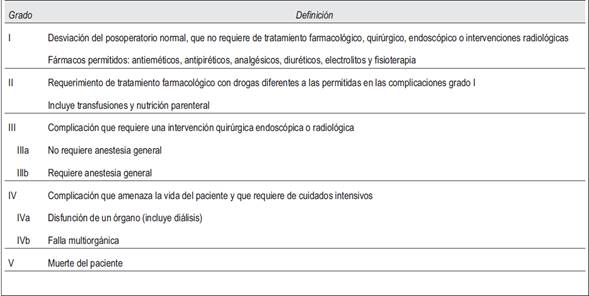

Para cada caso se consignó edad, sexo, tamaño de la lesión, método imagenológico de detección y motivos por los que fue indicado, estudios de valoración funcional cortical y medular (cortisol plasmático, prueba de supresión de dexametasona, aldosterona, metanefrinas y ácido vanililmandélico en orina), vía de abordaje quirúrgico (convencional o laparoscópica), duración del procedimiento, estadía hospitalaria posoperatoria, anatomía patológica definitiva y complicaciones, utilizando para las últimas la clasificación de Clavien-Dindo(Tabla 1). La información fue obtenida a partir de las historias clínicas de los pacientes y se recogió en una planilla Excel para su posterior análisis.

Se registraron las siguientes complicaciones, todas clasificadas como grado III siguiendo la clasificación de Clavien: una lesión duodenal (en cirugía laparotómica) detectada y reparada en el intraoperatorio, con buena evolución posterior; un sangrado intraoperatorio de la logia suprarrenal; una lesión esplénica que requirió la esplenectomía también por vía laparoscópica. No se registraron muertes a causa de estas complicaciones.